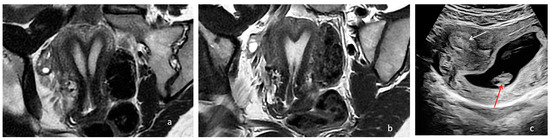

The resectoscope was placed into the right hemi-uterus, while a 12 Fr Foley catheter was inserted into the left hemi-uterus to provide guidance (Figure 1). The uterine septum was removed using the Collins knife, starting from the isthmic area and moving towards the uterine fundus, with the interostial plane as the limit for resection.

Figure 1. Hysteroscopic resection of the uterine septum in a patient diagnosed with U2bC2V1 anomaly using the Collins knife (blue arrow) and a Foley catheter inserted into the left hemi-uterus (white arrow); S (uterine septum).